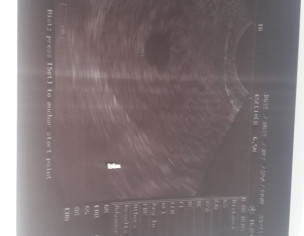

She is married since march. And first time she conceived in may but she had miscarriage after 1 month. Now again she is pregnant. And her last periods date is 6 October. There is a sake scene in the ultrasound report but no baby or baby’s heart is seen. Her gynaecologist suggested her dephaston and folic acid. And told her complete bed rest. I will post the report and please guide me what should she do?

- dear there might be hormonal imbalance history and at present could be date discrepency or not enough hormonal support for pregnancy .

- resscan after 10 days ,report immediately to Gynae if Symmptoms lie pain or bleeding appear.